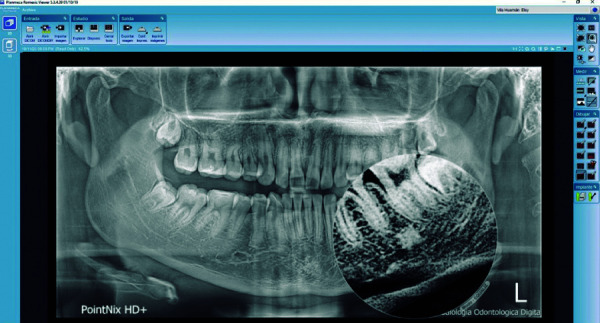

Objective: The objective of this study was to determine, describe and identify the prevalence of radiopaque images compatible with idiopathic osteosclerosis in digital panoramic radiographs taken in patients between the ages of 18 and 50.

Materials and methods: The study design was descriptive, cross-sectional and retrospective. The sample consisted of 500 digital panoramic radiographs taken between January 1, 2016 and December 31, 2018, in the target population aged between 18 and 50 years from Ayacucho - Peru, attended at a private radiological center. The radiographs obtained were analyzed using the Romexis viewer version 5.3 program, and the results were recorded on a data collection sheet. The Chi-square test was used to establish associations among the variables evaluated. A P <0.05 was considered significant.

Results: 500 digital panoramic radiographs were analyzed, showing a prevalence of idiopathic osteosclerosis of 17.4%, of which 12% were female and 5.4% male, and according to age, the presence of idiopathic osteosclerosis was more prevalent in the second decade of life.

Conclusions: It is important to have a clear differential diagnostic criterion when distinguishing the different radiopacities such as idiopathic osteosclerosis, which can occur in the jaws, making a precise record of the morphometric characteristics and monitoring over time, taking into account their existence and implication in dental treatments.